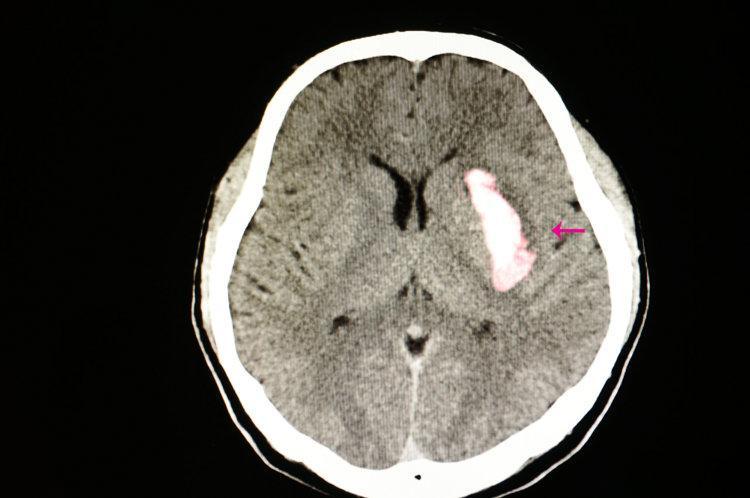

到了醫院,醫生一量血壓,哎呀,不得了,竟然高到190/110mmHg!醫生趕緊給他做了頭部CT,結果確診是腦溢血

腦出血,俗稱“腦溢血”,是非創傷性腦內血管破裂導致腦實質聚集血液的一種疾病。腦出血的發病十分迅速,而且危險性極大,有關數據顯示,腦出血發病一月內死亡率高達35%-52%,發病六個月有80%存活患者遺留有殘疾問題,給社會和家庭都帶來沉重負擔。